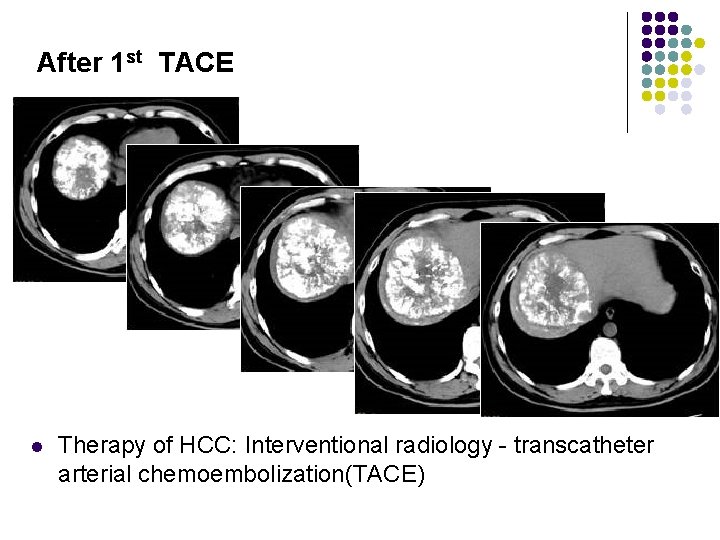

After 1 st TACE l Therapy of HCC: Interventional radiology - transcatheter arterial chemoembolization(TACE)